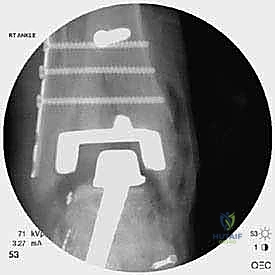

* دمج الكاحل (Ankle Arthrodesis): إذا كان التآكل العظمي هائلاً ولا يسمح بتركيب مفصل جديد، يتم إزالة المفصل الصناعي ودمج عظمة الساق مع عظمة الكاحل باستخدام مسامير وصفائح معدنية وطعوم عظمية.

علاج هذه الكسور يتطلب مهارة فائقة من الدكتور محمد هطيف، حيث يتم استخدام تقنيات الجراحة الميكروسكوبية وتثبيت الكسور باستخدام صفائح معدنية دقيقة ومسامير (Locking Plates) دون المساس بثبات المفصل الصناعي، أو يتم دمج علاج الكسر ضمن عملية مراجعة المفصل الكلية إذا كان المفصل نفسه تالفاً.

الخطوة الخامسة: تركيب المفصل الجديد أو الدمج

يتم إدخال المفصل الجديد المخصص للمراجعة، والذي يحتوي غالباً على سيقان (Stems) تدخل عميقاً في عظمة الساق وعظمة الكاحل لضمان الثبات الميكانيكي. في حال وجود كسور في الكعب، يتم تثبيتها في هذه المرحلة.

يتم خياطة الأربطة والأنسجة الرخوة والجلد بطرق تجميلية دقيقة لتقليل الندبات وسرعة الالتئام، ثم توضع القدم في جبيرة خلفية واقية.